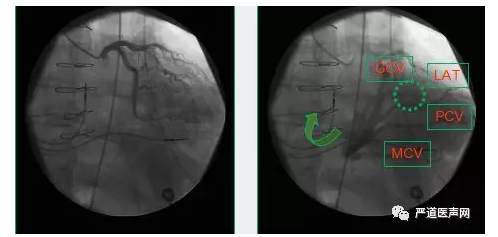

寻找CS开口方案四:顺向性冠状静脉显影